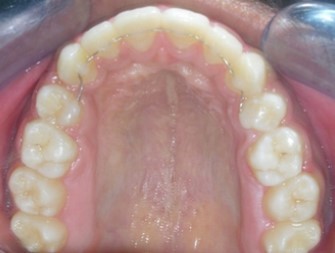

Figure 7e.Post-treatment intra-oral-Upper occlusal

Figure 7f.Post-treatment intra oral-Lower occlusal

Post treatment lateral cephalometric radiograph was taken to assess the treatment changes. (Figure 9). The changes in maxilla in the anteroposterior direction was insignificant, however an increase in the length of the mandible measured from Condylion (Co) to Gnathion (Gn) and an increase in anterior facial height was observed. Maxillary incisors were retracted dramatically by 8mm and the mandibular incisors were proclined by 3mm to camouflage the skeletal class II malocclusion.(Table 1). Effective expansion of the maxillary constriction as an end-of treatment goal was achieved. (Figure 10a,Figure 10b).